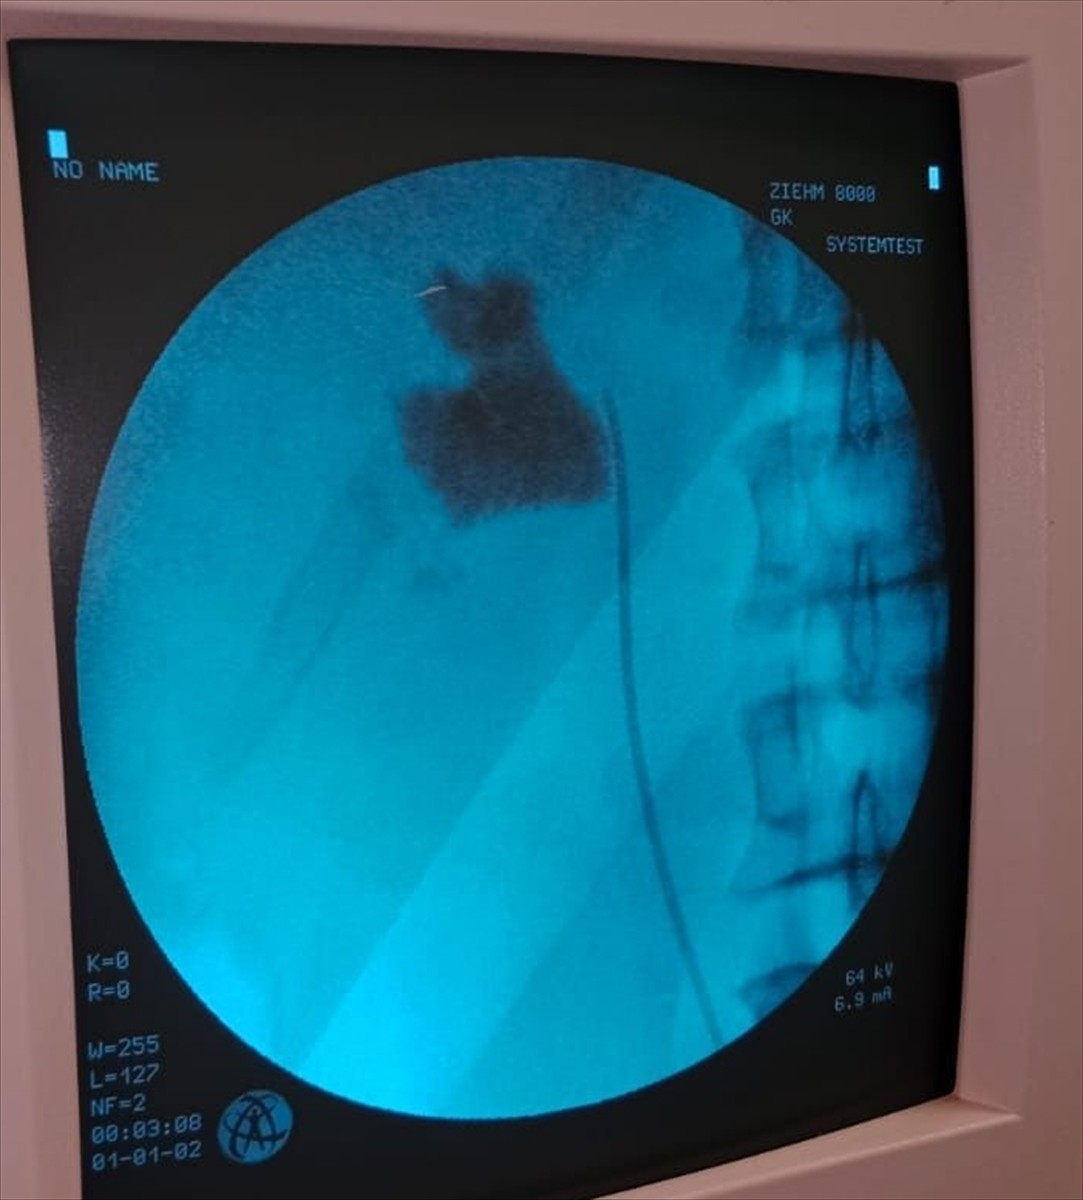

Üroloji Kliniği'nden Uzm. Dr. Talip Göktaş liderliğindeki ekip, hastanın böbreğindeki taşı kapalı ameliyat yöntemiyle başarıyla çıkardı. Dr. Göktaş, "Hastamızın sol böbreğinde yaptığımız kontrollerde 6 cm'lik bir taş tespit ettik. Kapalı böbrek taşı yöntemi PNL ile ameliyatı gerçekleştirdik," dedi.

Kırşehir'de bir hastanın böbreğindeki 6 santimetrelik taş, kapalı ameliyatla alındı. Kırşehir Eğitim ve Araştırma Hastanesi Üroloji Kliniğinden Uzm. Dr. Talip Göktaş (ortada) ve ekibi tarafından kapalı ameliyatla İlhan Çakır'ın (solda) böbreğindeki taş başarılı bir şekilde çıkarıldı.